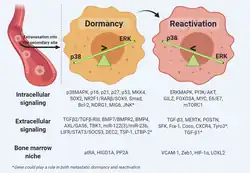

Les cellules dormantes

Par définition, la dormance du cancer est une phase d'arrêt de la progression du cancer qui survient pendant la phase de formation de la tumeur primaire ou après l'invasion de sites secondaires [130]. La dormance métastatique se produit spécifiquement en raison de l'acclimatation retardée des cellules cancéreuses en diffusion vers leurs niches secondaires [131] et affecte des cellules envahissantes uniques. ou des grappes de cancer après circulation.

Chez de nombreux survivants du cancer, les cellules cancéreuses dormantes sont présentes longtemps après l'ablation radicale de la tumeur primitive et seraient responsables de rechutes tardives [131]. Deux mécanismes de dormance existeraient: la dormance angiogénique dans laquelle un équilibre est réalisé entre la division cellulaire et la mort cellulaire par absence de vascularisation des cellules cancéreuses et la dormance à médiation immunitaire dans laquelle la masse tumorale est préservée de la cytotoxicité des cellules immunitaires [132],[13]. Certains pensent que le microenvironnement de l'organe cible ordonne aux cellules tumorales circulantes d'entrer en dormance, tandis que d'autres pensent que les tumeurs primaires précodent une signature de dormance sur les cellules tumorales circulantes qui s'activent lorsque les cellules tumorales circulantes pénètrent dans le microenvironnement hôte. Une autre explication possible est que la dissémination précoce engendre des cellules tumorales circulantes qui répondent aux signaux induisant la dormance et entrent en dormance dans les organes cibles [133].

Mécanismes moléculaires de la dormance

La régulation de la dormance des cellules tumorales implique des interactions réciproques entre l'environnement et les mécanismes qui contrôlent les programmes transcriptionnels [134]. La dormance unicellulaire décrit l'état de quiétude réversible dans lequel la cellule métastatique entre en réponse à des stimuli stressants, tout en exprimant le marqueur de prolifération Ki67 [130]. L'homéostasie métabolique est maintenue à l’état dormant grâce à la régulation négative de deux des voies les plus étudiées qui sont activées au cours de l’oncogenèse, les voies de signalisation RAS – MEK – ERK/MAPK et PI3K-AKT, qui jouent un rôle essentiel dans la gouvernance de la dormance des cellules cancéreuses [135].

Les facteurs sécrétés par les niches pré-métastatiques , tels que les protéines morphogénétiques osseuses dérivées des cellules mésenchymateuses et le growth arrest – specific 6 (GAS6), déplacent les cellules cancéreuses vers la dormance [136],[137]. Le facteur de croissance BMP7 active le gène suppresseur métastatique NMYC, gène régulant négativement la proteine NDRG1, entraînant une augmentation de l’activation de la kinase p38 , de l’expression de l’inhibiteur du cycle cellulaire p21 entraimant l’arrêt du cycle cellulaire [136].

Les interactions moléculaires entre la signalisation induite par les mitogènes et celle induite par le stress sont essentielles à la régulation de l'état de dormance/activation des cellules cancéreuses métastatiques. Le rapport entre le signal extracellulaire ERK1/2 et la la kinase p38 régule le cycle cellulaire. Des niveaux élevés d'activité ERK1/2 favorisent la prolifération, tandis que des niveaux élevés de p38 favorisent la dormance. L'activité accrue de la kinase p38 déclenche l'activation de la réponse protéique , qui régule positivement l'activation du facteur de transcription 6, favorisant ainsi l'arrêt et la survie des cellules [138],[139]. L'activation des voies de signalisation du stress induit un état de quiétude soutenu lié à dormance.

Réveil des cellules dormantes

Les chercheurs ont commencé à comprendre le processus qui permet à certaines cellules cancéreuses de devenir dormantes pendant un certain temps et de réapparaître plus tard avec une maladie récurrente. Ces cellules cancéreuses entrent dans un état de latence et de division lente en inhibant une voie de signalisation pilotée par la protéine WNT [144].De plus, ces cellules présentent des niveaux accrus des gènes de cellules souches SRY-box et SOX9, qui permettent la croissance de nouvelles tumeurs si certaines conditions existent. Pour réduire la capacité du système immunitaire à les identifier, ces cellules cancéreuses dormantes régulent négativement l’expression de molécules reconnaissables par les cellules immunitaires [144]. Cela permet aux cellules tumorales d’échapper à une réponse immunitaire jusqu’à ce que les conditions permettent le développement de métastases. Une inflammation persistante de l’organe hôte et l’établissement de pièges extracellulaires neutrophiles peuvent transformer les cellules cancéreuses dormantes en métastases agressives [145]. D’autres pensent que le passage de la dormance à l’activation se produit en ce qui concerne l’organotropisme [146] , indiquant que le microenvironnement de l’hôte joue un rôle dans le réveil des cellules. de leur état de dormance [147].Plus important encore, il a été établi que des niveaux élevés d'ERK1/2 par rapport à p38 MAPK favorisent la réactivation.